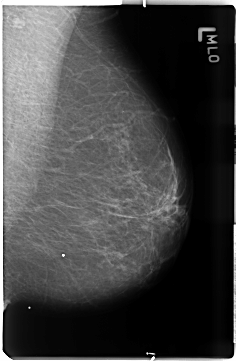

FILE: B_3506_1.RIGHT_MLO.OVERLAY

TOTAL_ABNORMALITIES 1

ABNORMALITY 1

LESION_TYPE MASS SHAPE FOCAL_ASYMMETRIC_DENSITY MARGINS ILL_DEFINED

ASSESSMENT 4

SUBTLETY 3

PATHOLOGY MALIGNANT

TOTAL_OUTLINES 1

BOUNDARY

B_3506_1.RIGHT_MLO

RIGHT_MLO LINES 4632 PIXELS_PER_LINE 3032 BITS_PER_PIXEL 12 RESOLUTION 50 OVERLAY